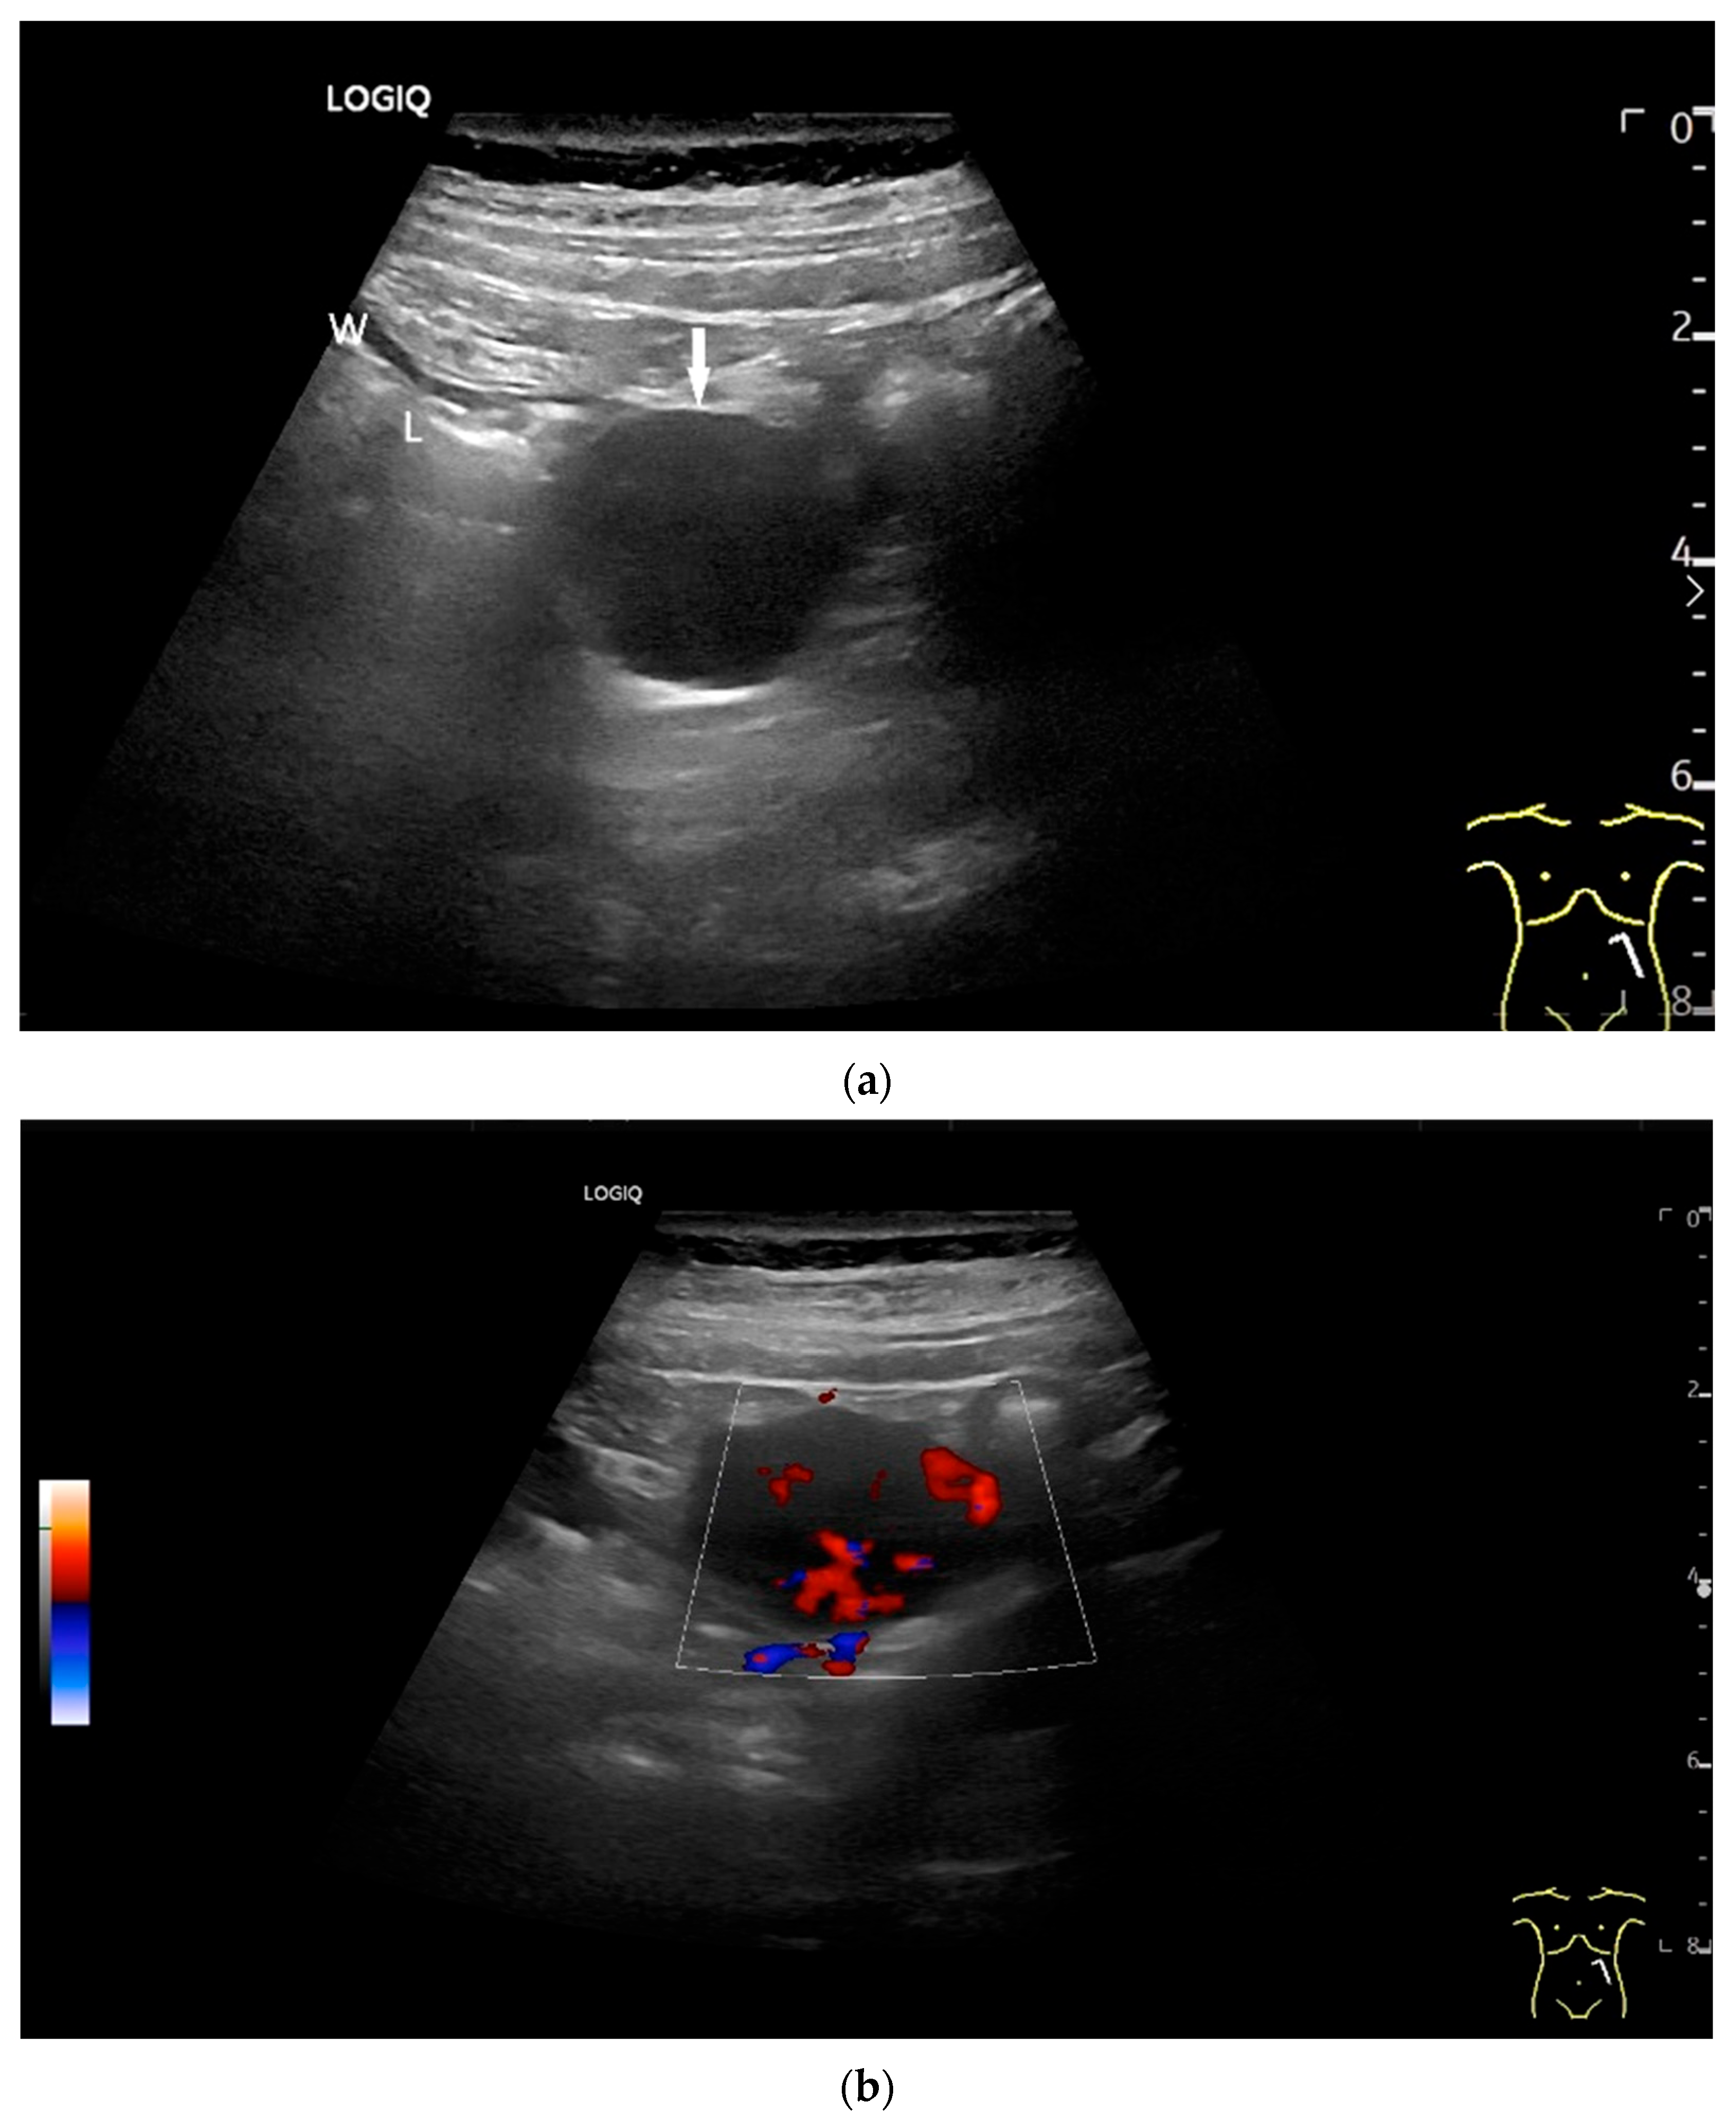

Figure 11.

GIST. A 30 mm large, very hypoechoic, almost anechoic round mass is visible in the left upper abdomen. This is located in the jejunum; the wall (W) and lumen (L) are visible (a). Macro vessels can be distinguished on Power Doppler, demonstrating that the lesion is solid and not cystic (b). On CEUS with 2.4 mL SonoVue (linear transducer 9 MHz), a small wheel-spoke-like vascular branching is visible at the margin (arrow) (c) with centrifugal enhancement (arrow) (d). Hyperenhancement is heterogeneous in the early arterial phase (e,f) and becomes homogeneous in the later course of the arterial phase (g). The extent of the heterogeneously enhanced tumor is marked with arrows (e). The intensity of the enhancement decreases during the first minute. The tumor is marked with arrows (h). Jejunal segment resection revealed the histology of an epithelioid GIST.

Figure 12.

GIST. Incidental finding of a 35 mm, slightly polycyclic, homogeneous hypoechoic mass in the left upper abdomen (a,b). This changes position with the movements of the small intestine. In CEUS with 1.2 mL SonoVue using the abdominal sector transducer (1–5 MHz), the mass shows homogeneous hyperenhancement in the arterial phase (c). The intensity then decreases (d). The tumor is marked with arrows in CEUS.